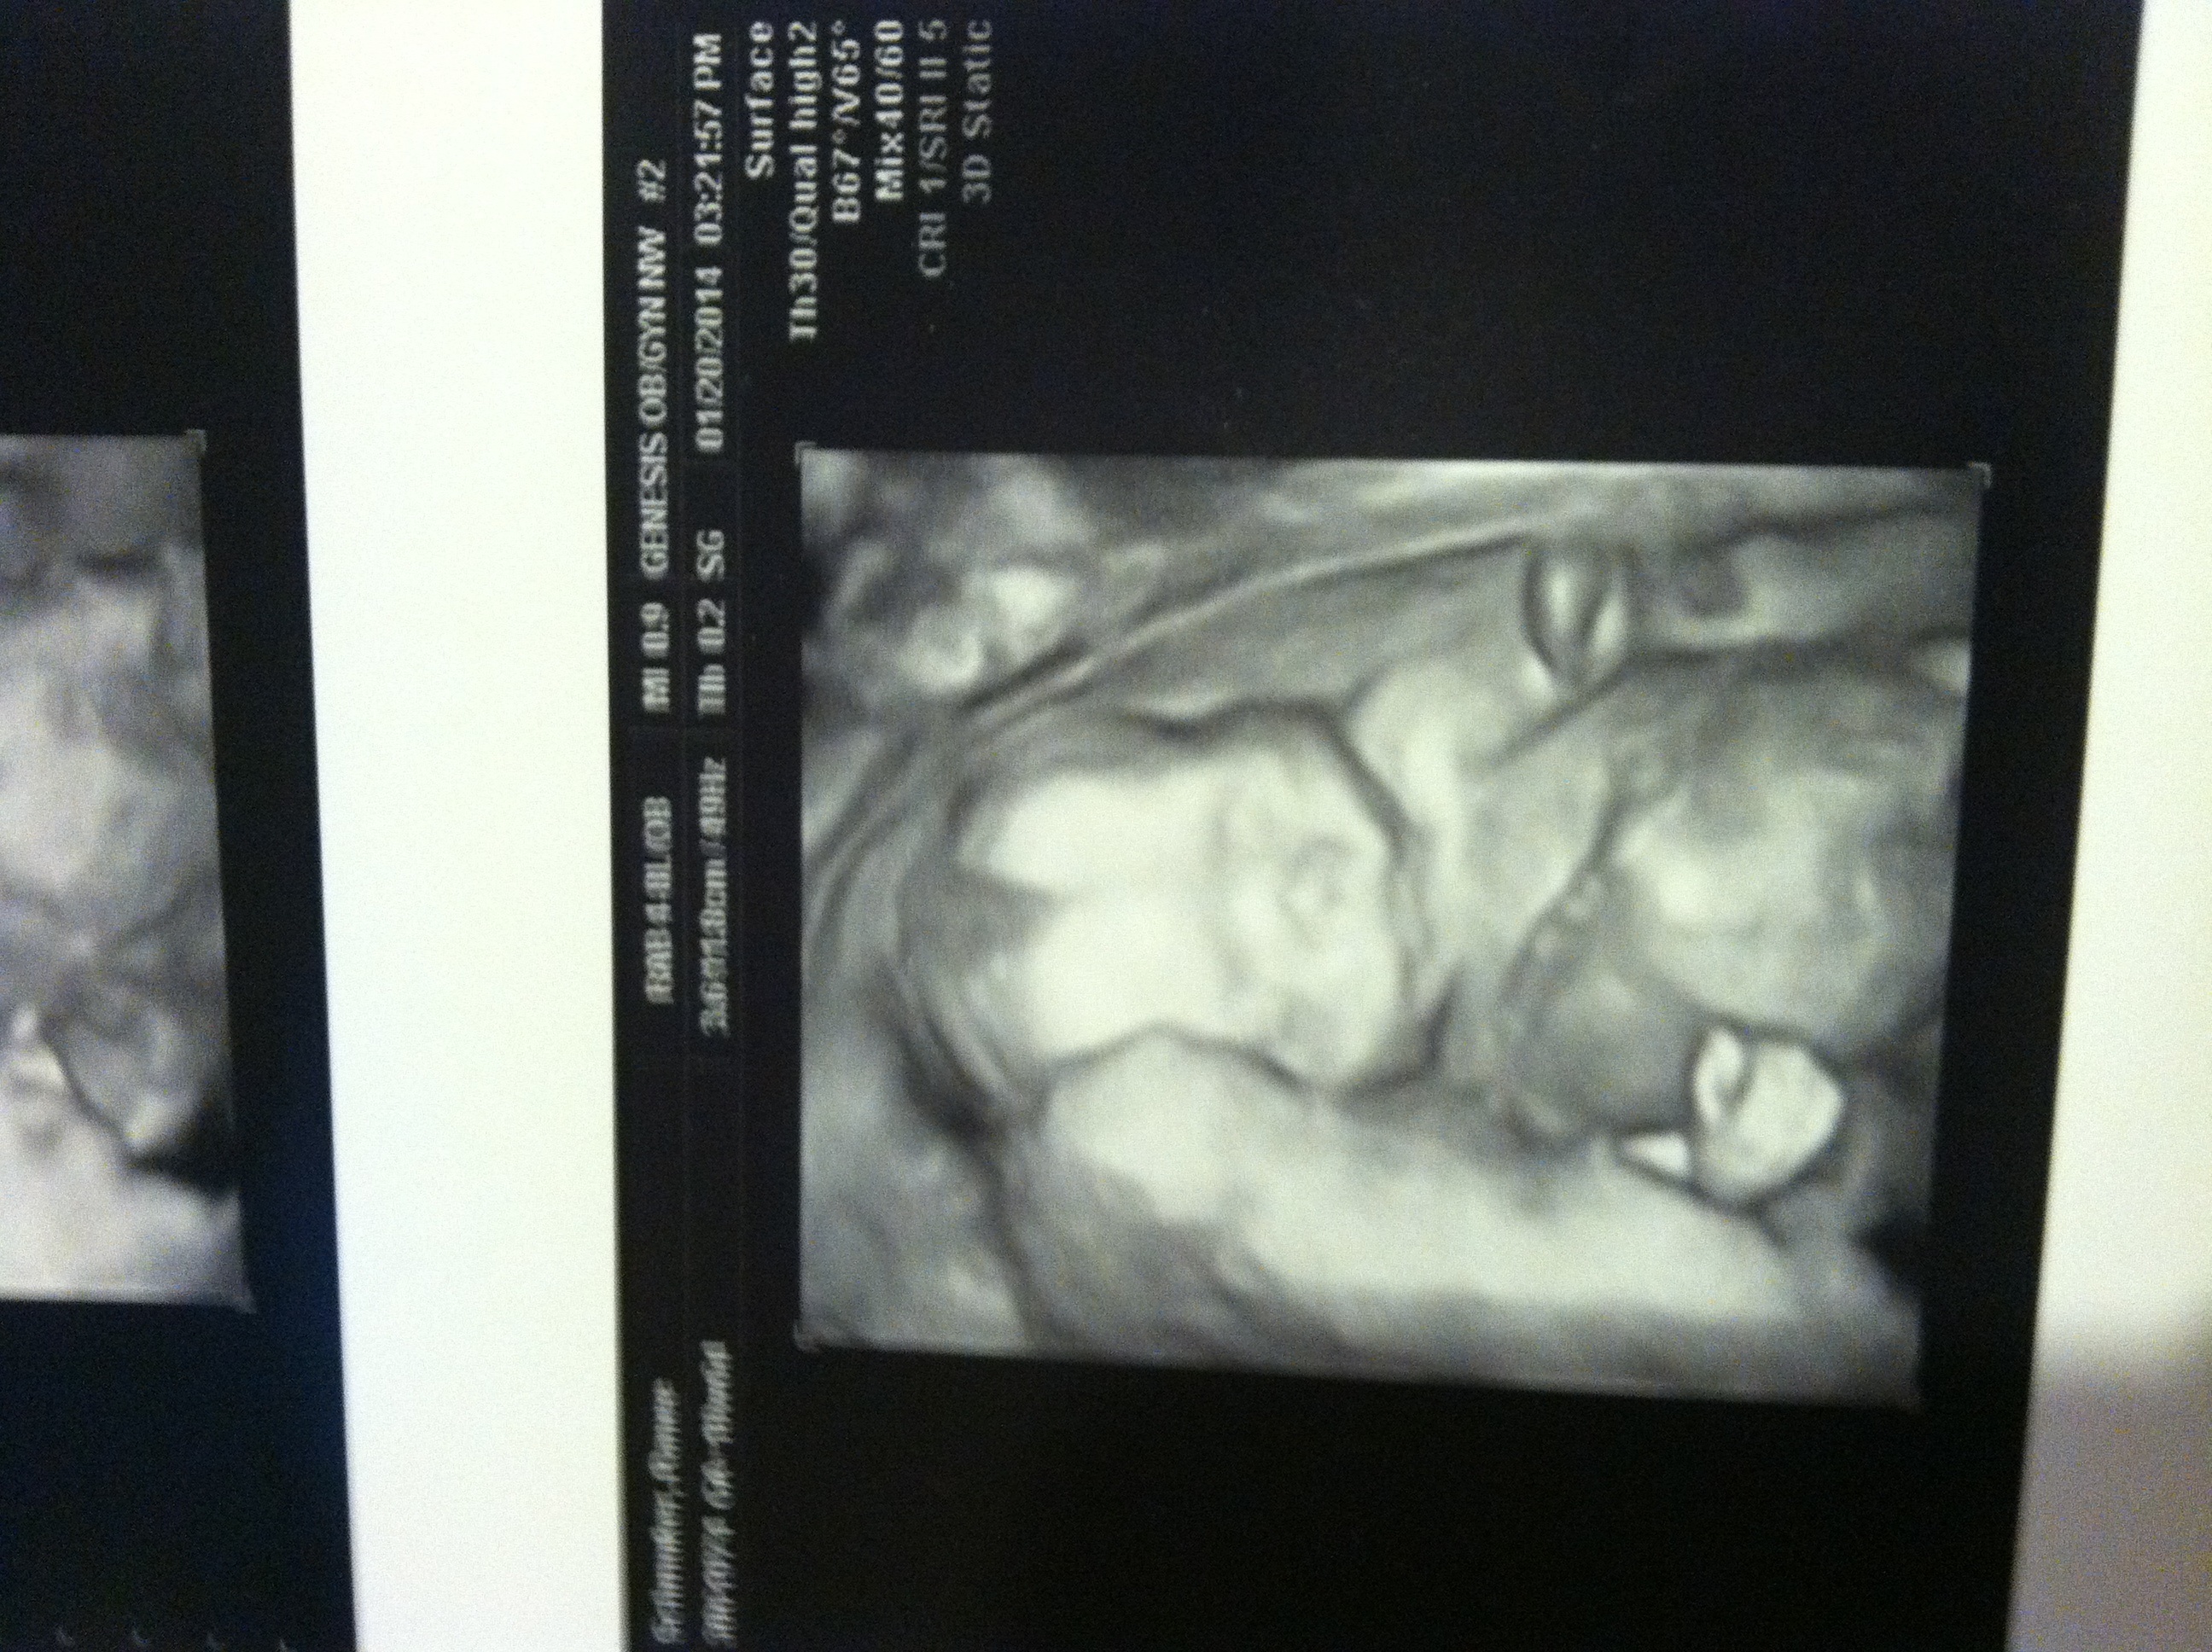

I'm late posting, but we found out we are having a boy yesterday. We didnt expect our doc to guve us a 3D shot, but he did :) My 8yr old son could not be more excited to have a brother on the way. We are due June 17. :). Congrats to all the mommies out there!!!